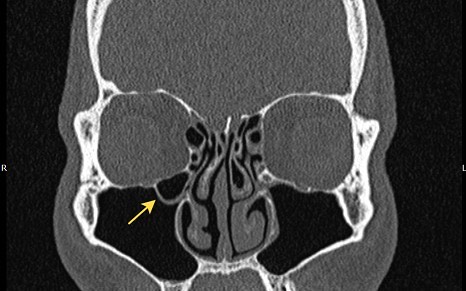

2397. Анатомическая структура, отмеченная на снимке, является